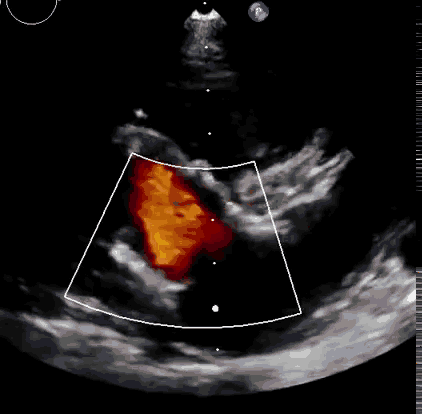

本次臨床前研究經右側頸靜脈置入LuX-Valve Plus輸送系統可調彎鞘管,在DSA及超聲引導下將人工三尖瓣瓣膜植入到原有三尖瓣位置,利用獨特的錨定技術將人工瓣膜支架可靠固定在預定的位置。

上海中山醫院葛均波院士、錢菊英院長、周達新教授、潘文志教授、潘翠珍教授、李偉教授共同完成此次臨床前研究。術后葛均波院士對Lux-Valve Plus的器械操作性能給予了高度評價,DSA和超聲影像也顯示出在本次研究中Lux-Valve Plus的安全性和有效性俱佳。